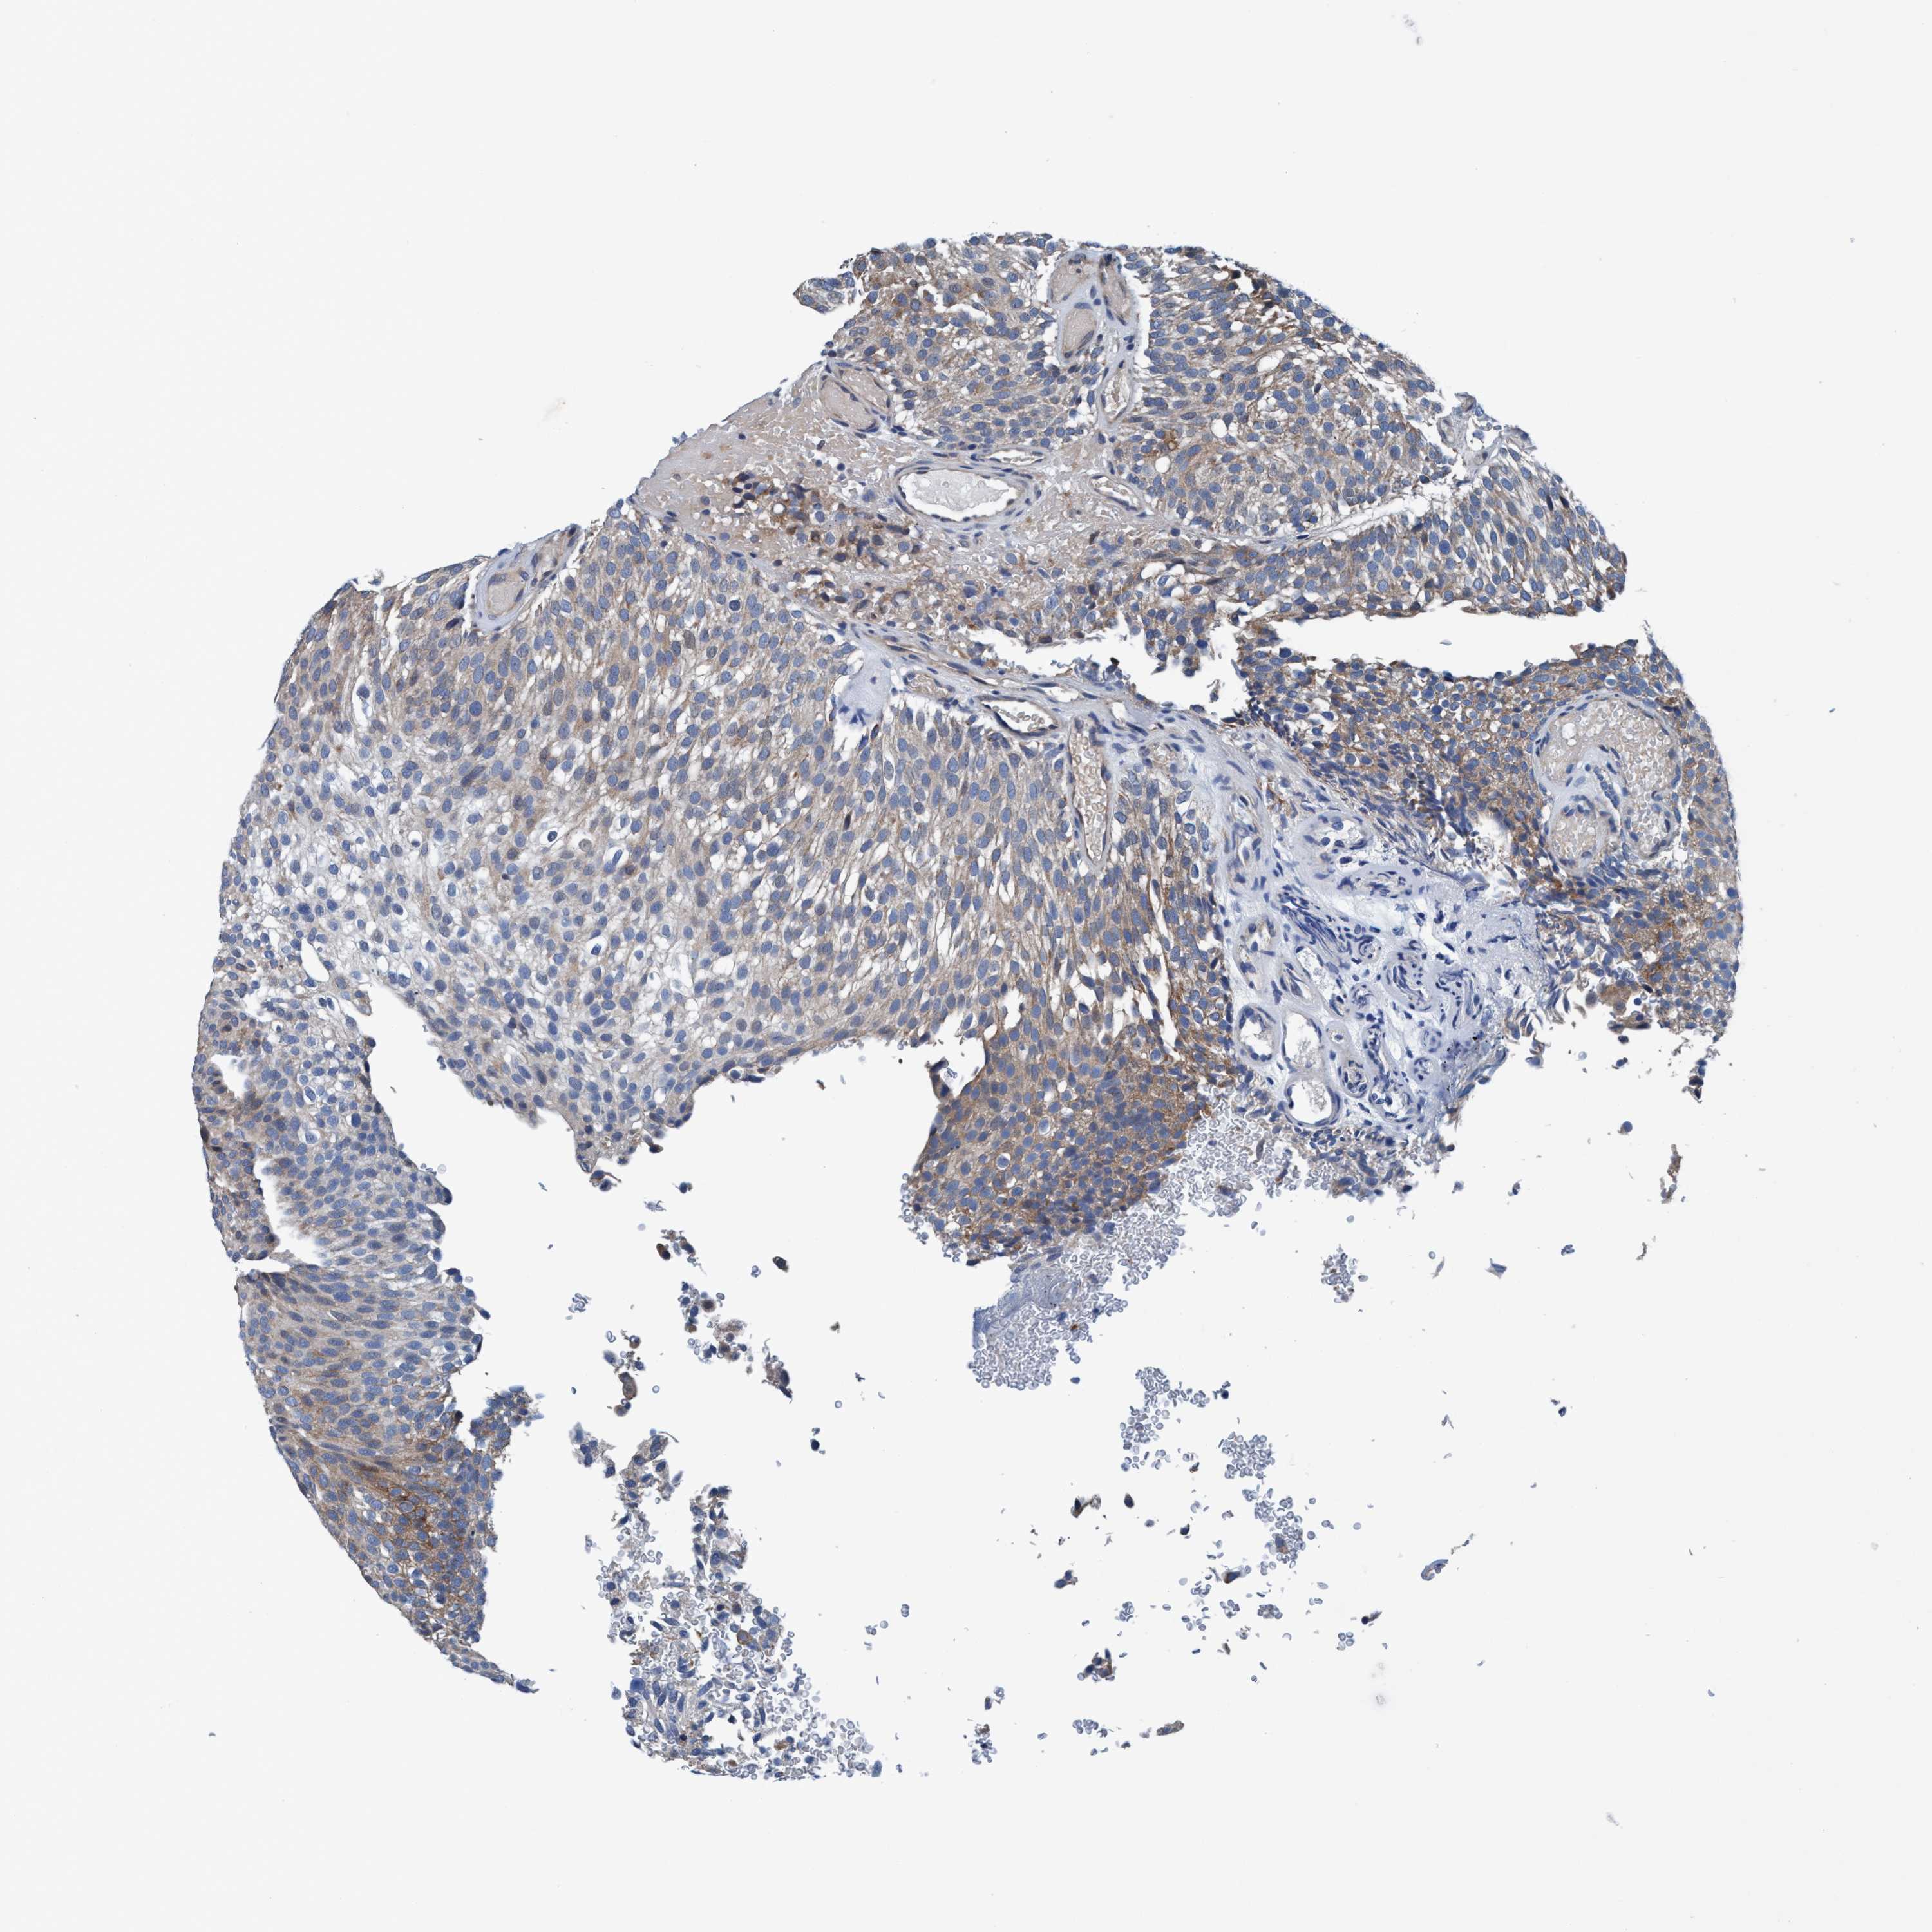

UROTHELIAL CANCER - Protein expressioni

A mouse-over function shows sample information and annotation data. Click on an image to view it in a full screen mode. Samples can be filtered based on level of antibody staining by selecting one or several of the following categories: high, medium, low and not detected. The assay and annotation is described here.

Note that samples used for immunohistochemistry by the Human Protein Atlas do not correspond to samples in the TCGA dataset.

Antibody stainingi

Antibody staining in the annotated cell types in the current human tissue is reported as not detected, low, medium, or high, based on conventional immunohistochemistry profiling in selected tissues. This score is based on the combination of the staining intensity and fraction of stained cells.

Each image is clickable and will lead to virtual microscopy that enables deeper exploration of all samples and also displays staining intensity scores, fraction scores and subcellular localization as well as patient and tissue information for each sample.

Antibody HPA008423

Staining

High

Medium

Low

Not detected

Intensity

Strong

Moderate

Weak

Negative

Quantity

>75%

75%-25%

<25%

None

Location

Urothelial carcinoma, Low grade

Urothelial carcinoma, High grade